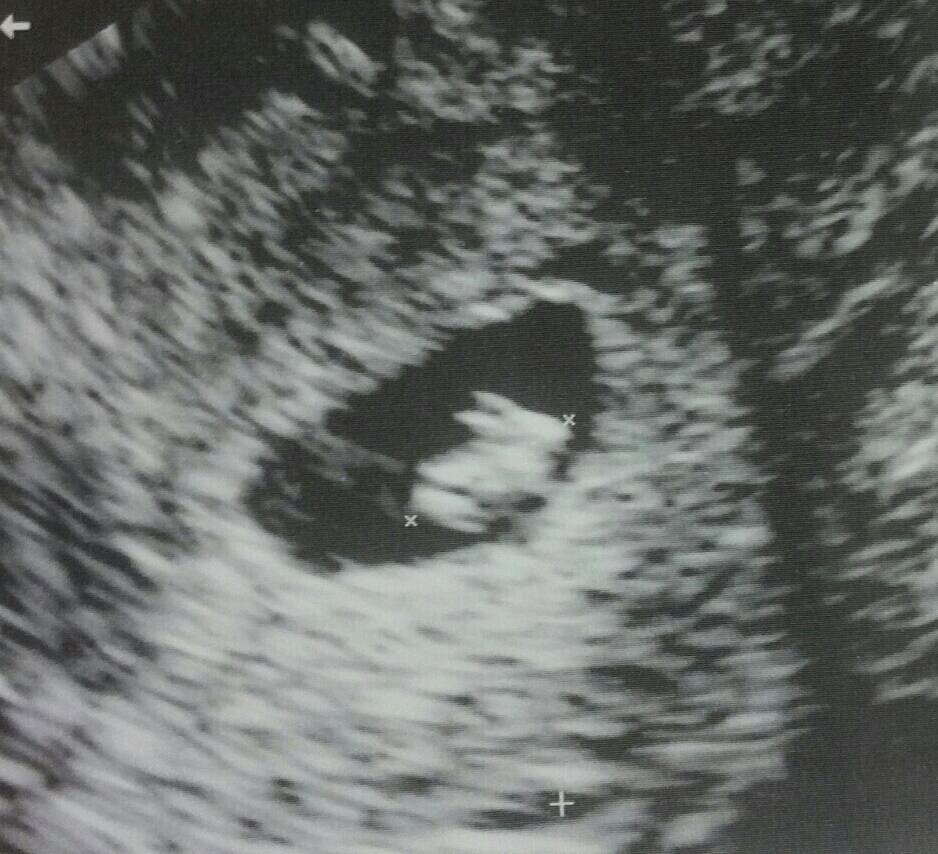

Una mamma ha condiviso su Reddit l’immagine dell’ecografia che ha fatto a 7 settimane  nella quale si nota qualcosa di strano e divertente!

Questa foto, assieme alla frase “Andata a fare la mia prima ecografia oggi…è uscito fuori che sto per avere un coniglio”, è stata condivisa migliaia di volte e diversi i commenti ironici:

Raccontando come è andata ha aggiunto “Ero nervosa perché abbiamo perso 2 bambini in passato così ero sollevata quando ho visto il battito cardiaco a 163. Poi quando abbiamo notato che si trattava di un coniglio abbiamo riso tanto“.

Infine ha aggiunto che il bambino è atteso per Aprile, una settimana prima di Pasqua.